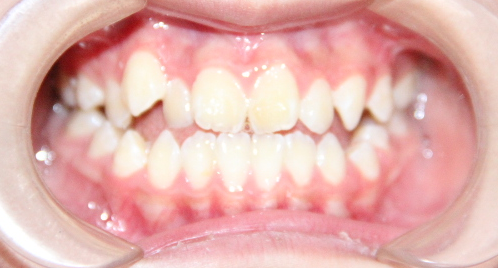

病例1

治疗后